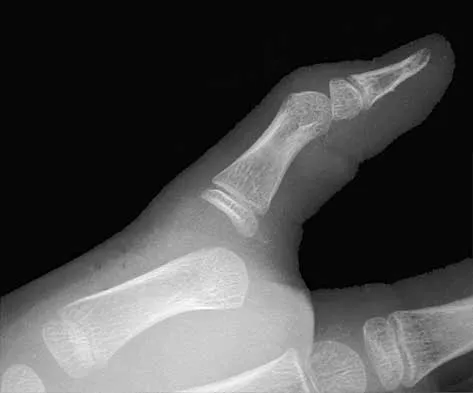

An active 47-year-old woman with rheumatoid arthritis reports forefoot pain and deformity and has difficulty with shoe wear. Examination reveals hallux valgus and claw toes. A radiograph is shown in Figure 10. What is the most appropriate surgical treatment?

Explanation

Rheumatoid arthritis commonly affects the metatarsophalangeal joints, which become destabilized with time resulting in hallux valgus and dislocated lesser claw toes. The result is metatarsalgia as the dislocated claw toes "pull" the fat pad distally. Severe hallux valgus reduces first ray load, which compounds the metatarsalgia because the load is transferred to the lesser metatarsal heads. First metatarsophalangeal arthrodesis restores weight bearing medially and corrects the painful bunion. Metatarsal head resection slackens the toe tendons to allow correction of the claw toes by whatever means necessary and decreases plantar load over the forefoot. Rheumatoid arthritis in the first metatarsophalangeal joint will continue to progress if osteotomies or a Lapidus procedure are performed. Keller resection arthroplasty increases transfer metatarsalgia and reduces push-off power during gait. Flexor-to-extensor tendon transfer of the lesser toes does not address the metatarsalgia and does not correct the dislocation of the metatarsophalangeal joint. Coughlin MJ: Arthritides, in Coughlin MJ, Mann RA (eds): Surgery of the Foot and Ankle, ed 7. St Louis, MO, Mosby, 1999, p 572.